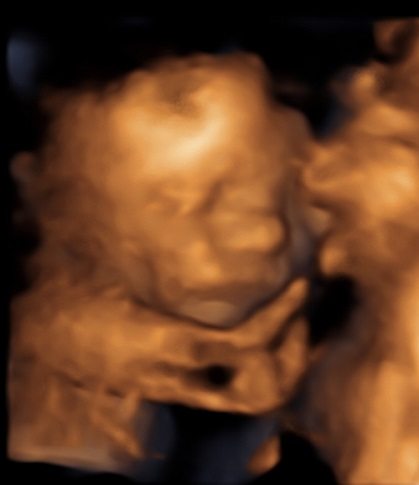

As soon as the baby’s face came onto the screen, the family was in complete awe. They began pointing out her facial features: button nose, rounded cheeks, similarities with big brother Dane, but the real magic happened when she decided to show the family her smile and the room just melted. As the viewing went on they connected while reminiscing about when Meagan was pregnant with Dane and bringing back memories from the soon-to-be new grandparents.

A sneak peak of Meagan & Thomas’ daughter